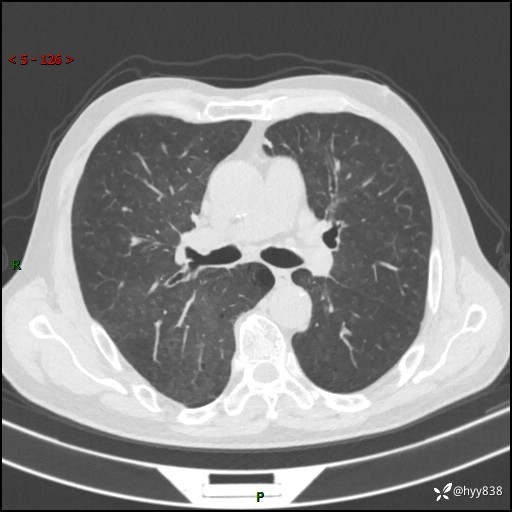

辅助检查:CT

胸部CT平扫